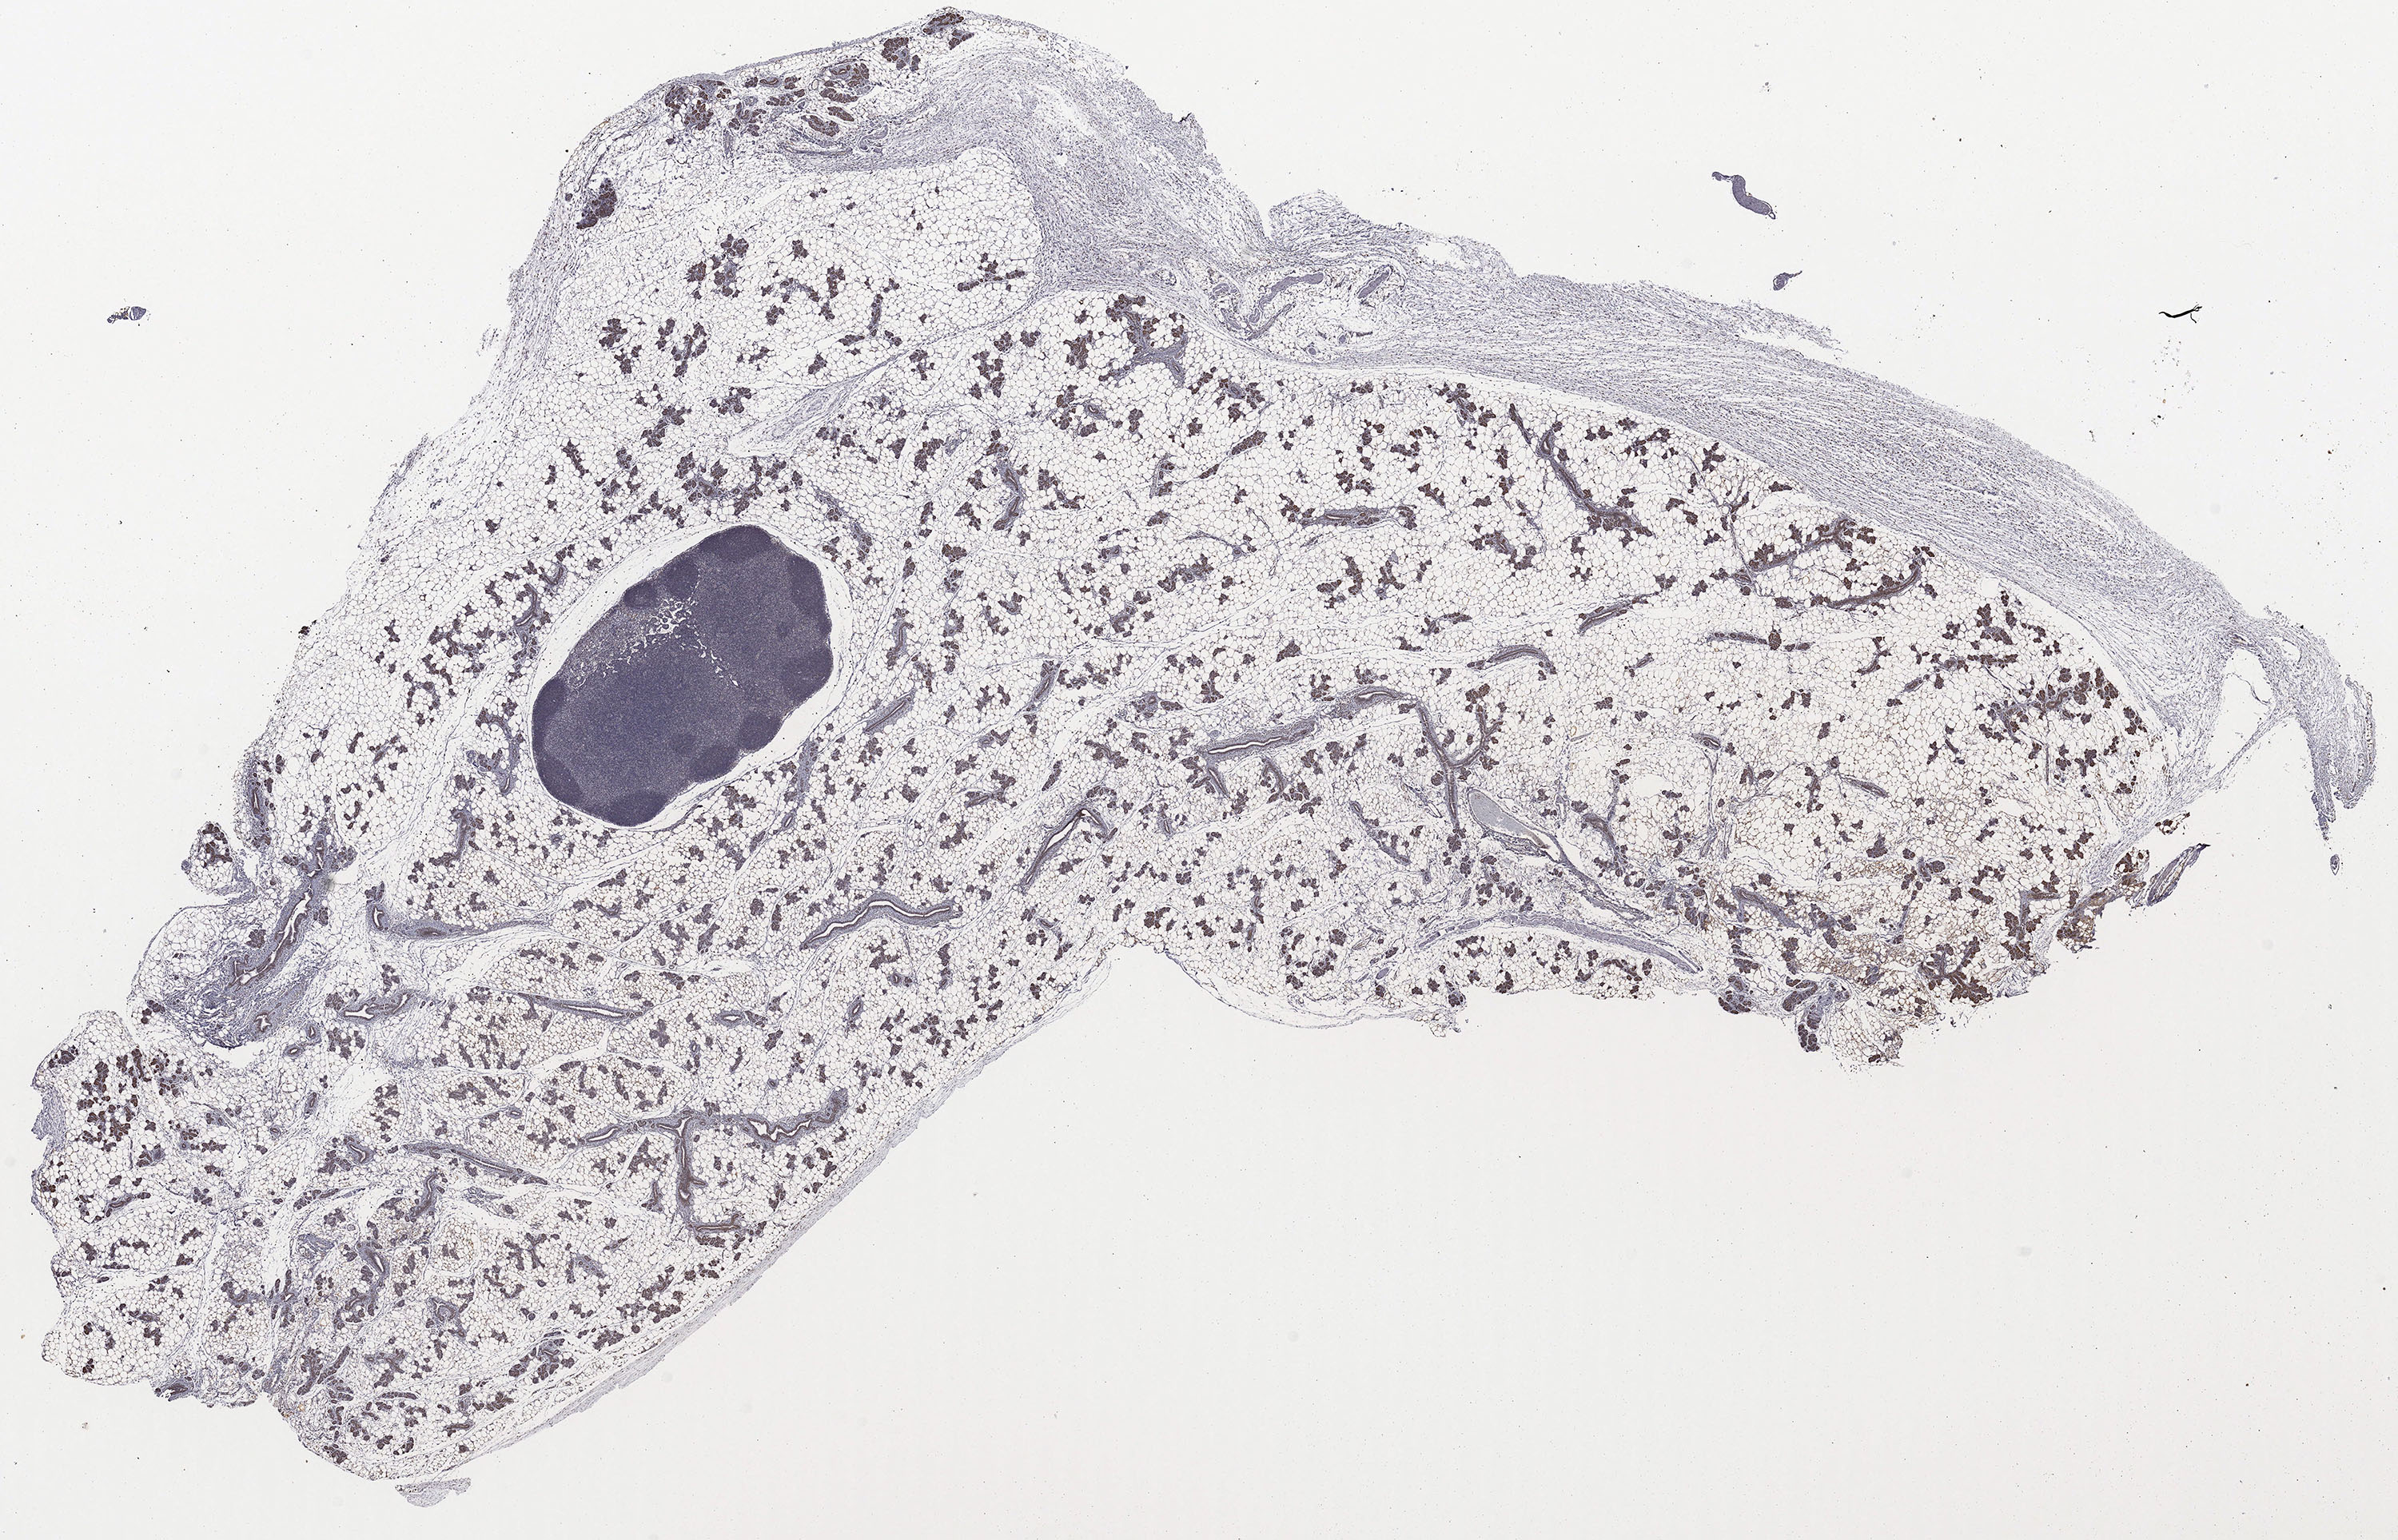

Adipophilin

Adipophilin:

Download a high resolution copy of the Adipophilin image.